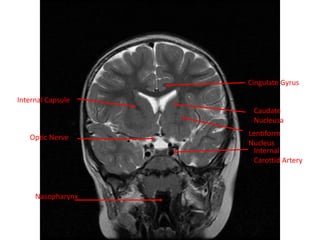

Internal Capsule

Caudate Nucleus

Optic Tract

Insula

Lentiform

Nucleus

Cingulate Gyrus

Optic Nerve

Nasopharynx

Internal

Carottid Artery

Caudate

Internal Capsule Cingulate Gyrus OpticNerve Nasopharynx Internal Carottid Artery Lentiform Nucleus Caudate Nucleusa